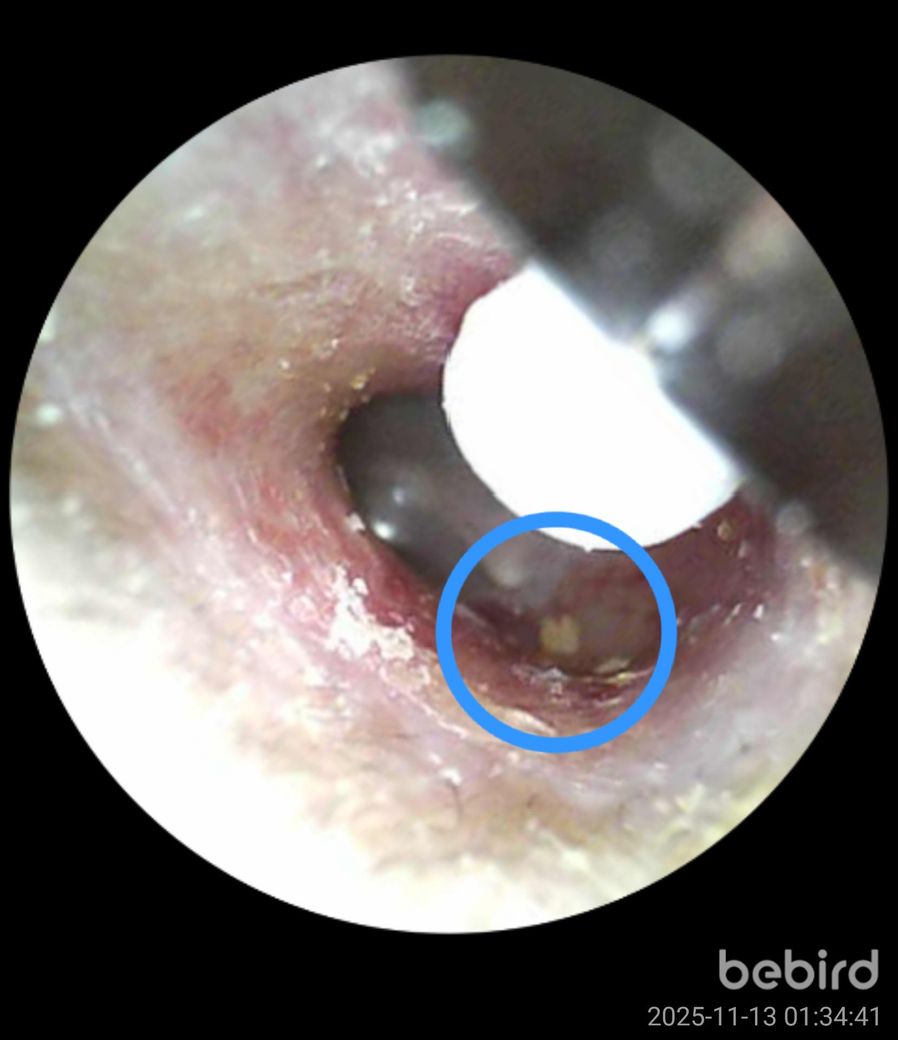

비버드를 가지고 주기적으로 귀를 확인하는 편입니다. 그런데 몇일째 고막근처에서 귀지처럼 보이는게 움직이지 않고 있는걸 확인했습니다. 처음 봤을때는 놔두면 나오겠지 싶어서 놔뒀는데 가만히 있는거보면 이물질인가 싶기도 합니다. 이거 귀지가 맞을까요?

• 2번 째 사진

올려주신 사진으로 미루어 귀지의 가능성이 생각되나 해상도가 낮아 감별이 어려우므로 이비인후과 진찰을 받을 것을 권합니다.